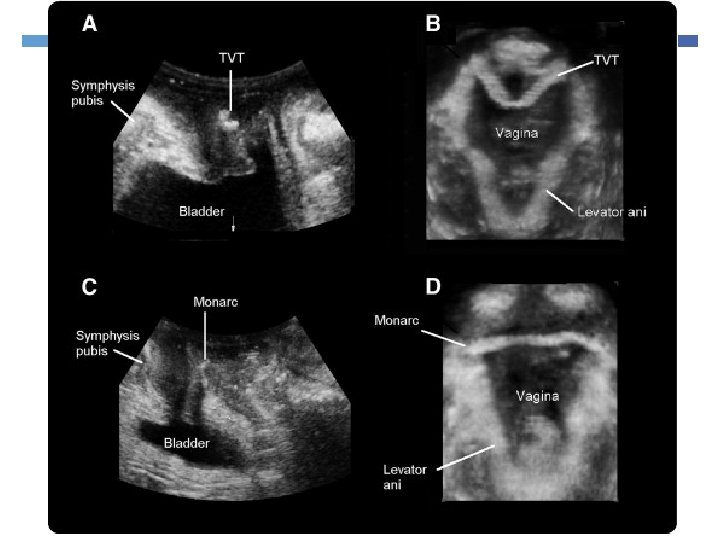

7. Evaluate sling complication

Imaging Slings Useful in voiding dysfunction post tape insertion Failed tapes Helps to see if tape has indeed been cut

Synthetic sling options for stress incontinence Retropubic Tension –Free Vaginal Tape (TVT) Transobturator Tape ( TOT)

RCT : Repeat surgery TOT vs TVT in women with ISD TVT 1: 16 TOT 1: 6 Do we need to look for Intrinsic Sphincter Deficiency (ISD)? Schierlitz et al 2008